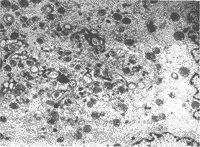

2.1.1 星形细胞瘤的一般形态学:星形细胞瘤瘤细胞单一,但细胞形态大小不规则,宽距离分布于树突状胞突之中;胞突与胞突之间的疏松网眼中有絮状无结构物或空白-微囊形成;胞浆内含大量胶质丝,缺乏细胞器;胞核外形极不规则,表面锯齿状,有的可见假性核内包涵体(图1),核染色质常贴近核膜;核分裂少。随着肿瘤分级的级数增高,瘤细胞更加密集,异型性更加突出:多形/怪异形核或多核,核分裂易见;胞浆内细胞器明显增多,有的出现发育不良的细胞器(图2),但仍可见胶质丝。无论星形细胞瘤分化程度高低,或是瘤细胞密度的高低,瘤细胞多弥漫排列,瘤细胞之间及其与瘤细胞突起间未见明显的细胞连接。一些瘤组织中尚可见神经元、神经轴突、树突及髓鞘等结构。

图1 显示核内假包涵体及核周胶质丝。

原放大为×13000

图2 显示瘤细胞浆内发育不良细胞器区。

原放大为×8300

自70年代电镜逐渐应用于病理诊断中,超微结构的研究开拓了认识肿瘤更深层次的视野。瘤细胞超微结构特征取决于组织学类型、分化和功能状态。国内外文献对星形细胞瘤已作了详细的描述[6,7],本研究的观察与文献相似,同时发现有些瘤细胞胞浆内发育不良的细胞器明显增多(图2),但仍可见少量胶质丝,这种瘤细胞的不协调性生长,是细胞分化与分裂失控在形态上的表达。有的可见假性核内包涵体(图1),这是由于细胞核表面积增大,核膜内折凹陷所致,反映瘤细胞代谢水平较高及生长活跃。关于细胞连接结构问题,据部分文献记载及个别作者观察仍可发现发育不良的粘着小体,而本观察中未找到明确的细胞连接,有待进一步探讨。观察中发现瘤组织中有神经元、神经轴突、树突及髓鞘等结构,可能与所取的样本有关,如取到肿瘤与脑组织交界处,就可以观察到神经的结构,表明肿瘤向脑组织内浸润性生长。